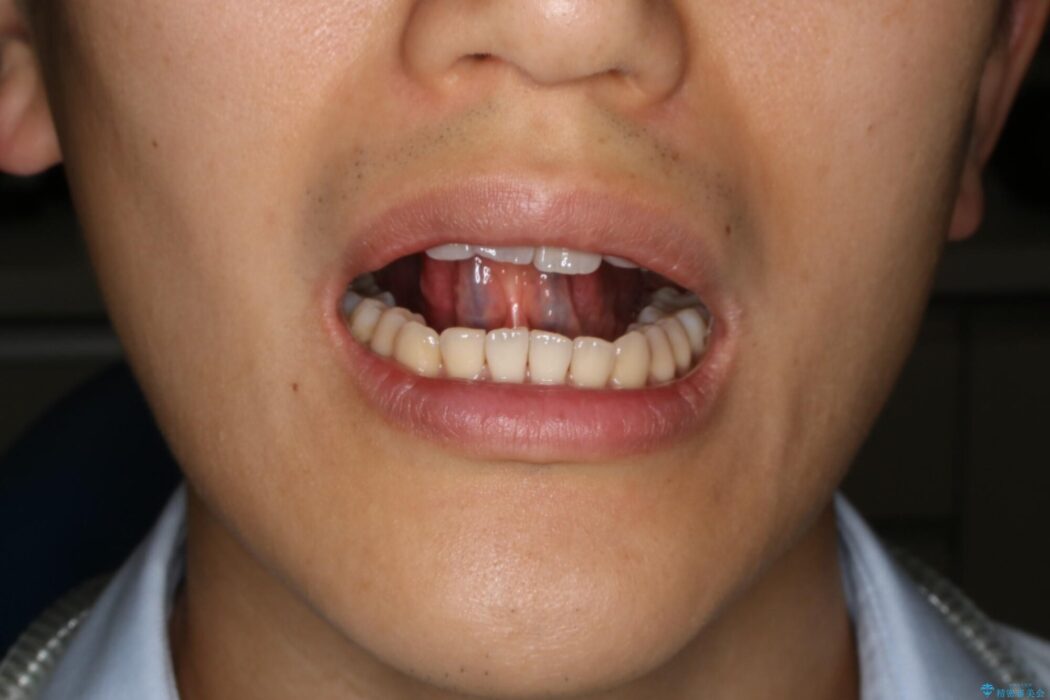

治療後について

舌小帯(舌の裏側についている線維性のスジ)を切除するだけでは滑舌は改善しません。ですが、舌小帯が短いことによって狭まっていた可動域が手術で広がり動きやすくなります。

手術と合わせて口周りの筋肉を鍛えて滑舌を改善していくことになります。

舌小帯切除術後、そのまま放置してしまうと切除した靱帯が元の短い状態で繋がってしまうことがあります。また手術前までで限られた範囲内のみで運動していた舌は通常の環境下の舌と比較して筋力か弱い傾向にあります。

手術効果を最大限に高めるためにも当院では「MFT(筋機能訓練)」を併用して行うことをおすすめしております。